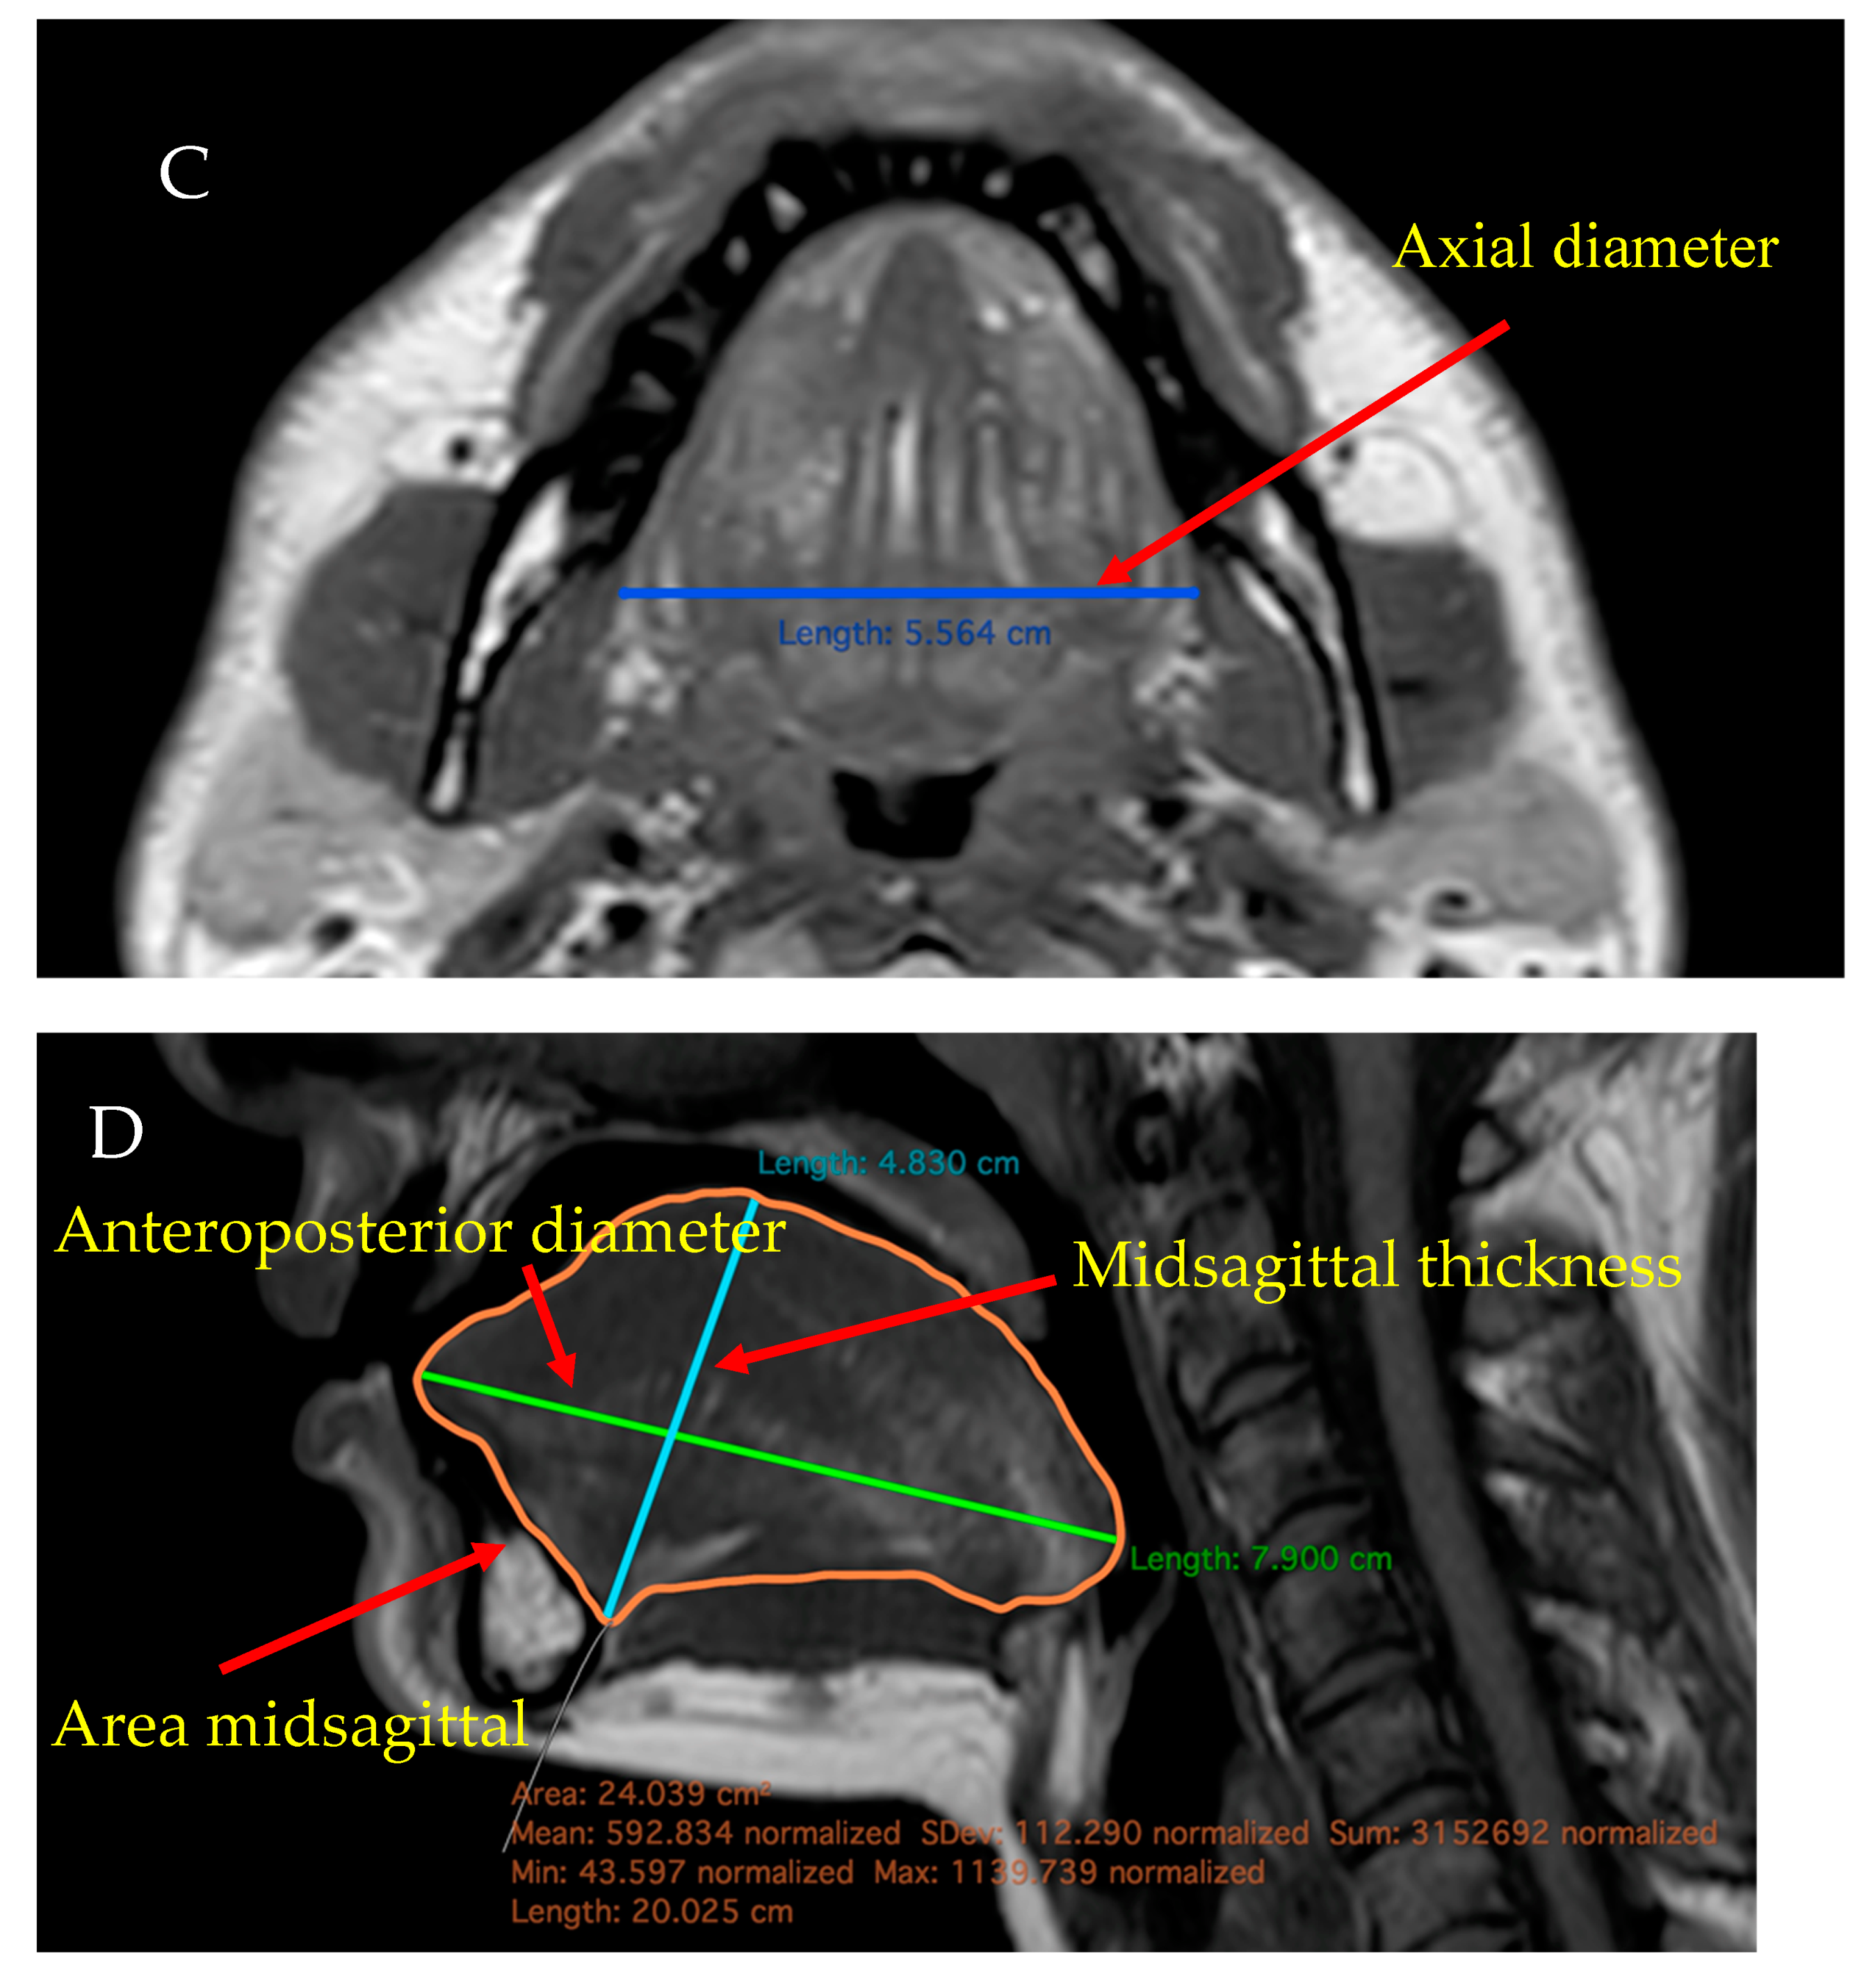

The sagittal diameter of the tongue was measured in the anteroposterior directions, as the longest diameter between the apex and the base of the tongue. Tongue thicknesses were defined as the longest diameters between the origin of the genioglossus muscle and the surface of the tongue. Both calculations were based on T2 and T1 TSE weighted images.

The coronal and axial diameters were defined as the longest laterolateral diameters in the coronal or axial direction in coronal T1 TSE, axial T2 SPIR and T1 TSE scans. The midsagittal area (cm2) means the surface measured in the middle line of the sagittal axis, which was determined using the DICOM viewer software. The volume of the tongue was calculated using a semiautomatised analysis software (Philips IntelliSpace Portal Multi-Modality Viewer). The measurement was based on the calculation of the Region of Interest and volume rendering.

Figure 2.

(A,D) sagittal, (B) coronal, (C) axial T1 TSE MRI scans showing the anteroposterior, axial, coronal, sagittal, and midsagittal diameters, and also the calculation of Fat% (taken from our data).